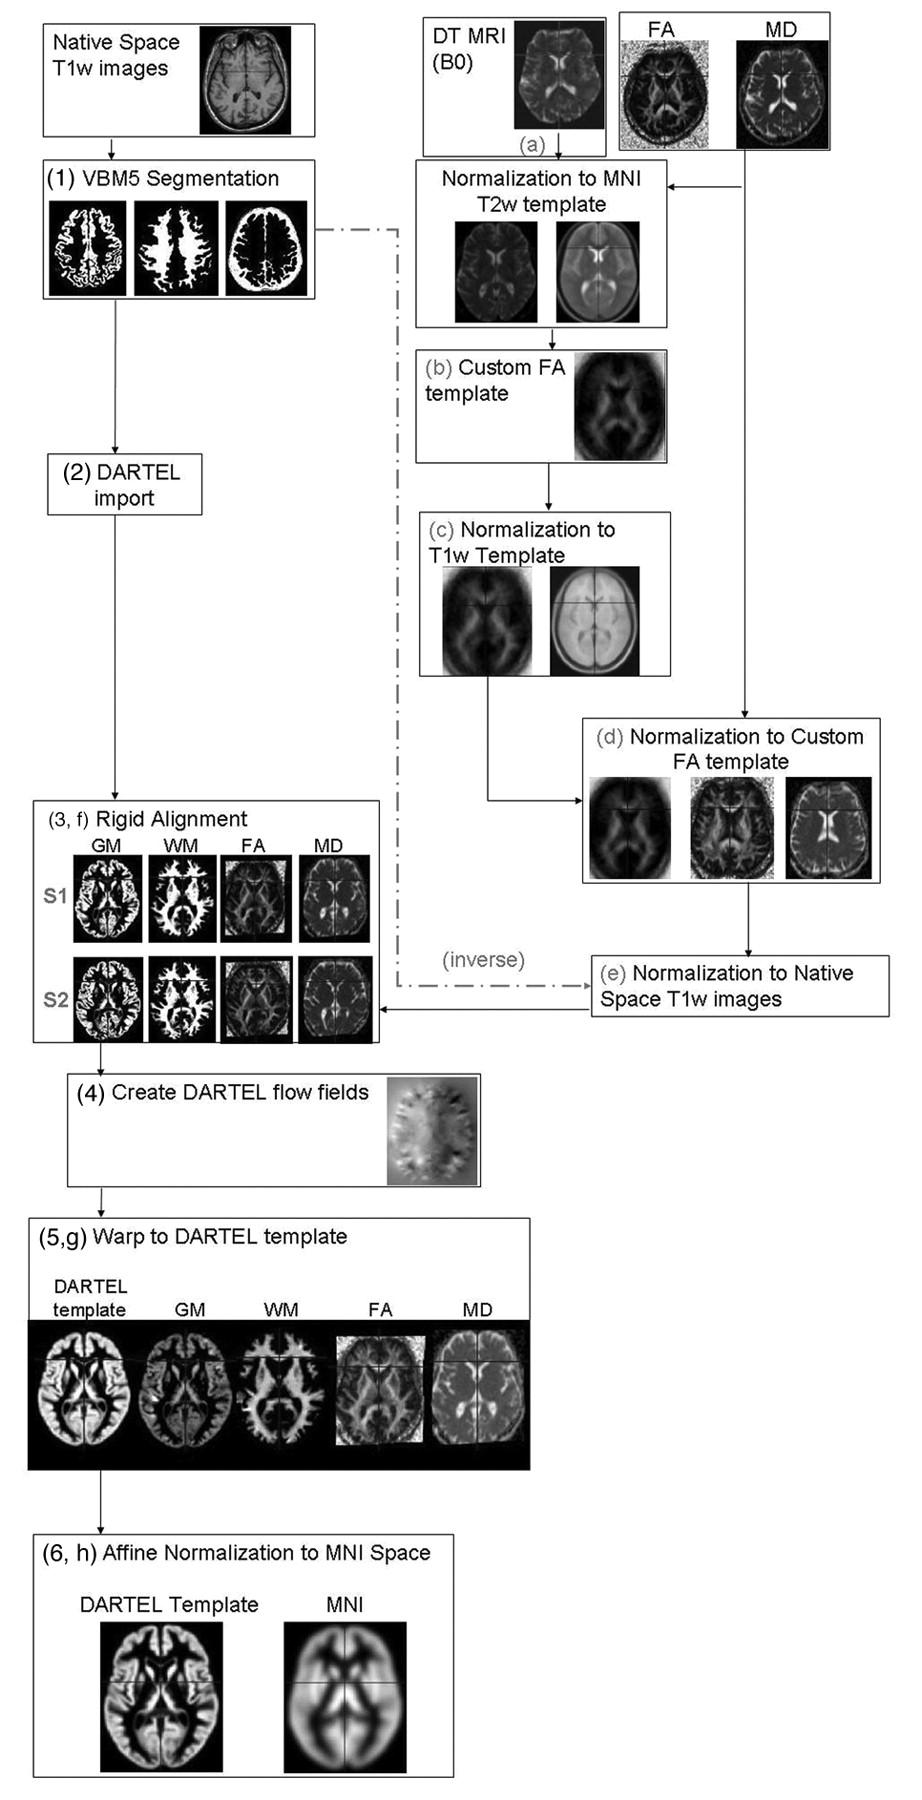

VBM was performed by using SPM5 (Wellcome Department of Imaging Neuroscience, London, United Kingdom) and the DARTEL registration method,28 as previously described.22 Briefly, the process was as follows: 1) T1-weighted images were segmented by using VBM5.1 toolbox (available at: http://dbm.neuro.uni-jena.de/beta-version-of-vbm51-toolbox/)29 to produce tissue probability maps in the MNI space. 2) The images were imported in DARTEL, 3) rigidly aligned, and segmented into gray and white matter (by using the segmentation parameters from the first step) and resampled to 1.5-mm isotropic voxels. 4) The gray and white matter segments were coregistered simultaneously by using the fast diffeomorphic image registration algorithm and the flow fields were created.28 5) The flow fields were then applied to the rigidly aligned segments to warp them to the common DARTEL space and then were modulated by using the Jacobian determinants. 6) The modulated images from DARTEL were normalized to the MNI template by using an affine transformation estimated from the DARTEL gray matter template and the a priori gray matter probability map without resampling (http://brainmap.wisc.edu/pages/8-Normalizing-DARTEL-Templates-to-MNI-Space).30 Before the statistical computations, the images were smoothed with an 8-mm FWHM Gaussian filter (see Fig 1 as a flow chart of the procedure).

Flow chart of the image processing streams. The text provides a description of the image-processing stream with numbers referring to T1-weighted processing and letters to DTI processing.

DTI analysis was performed by using in-house software. Diffusion-weighted images were first corrected for distortion induced by eddy currents31; then the diffusion tensor was estimated by linear regression5 and MD and FA maps were computed.4 To use gray and white matter volumes as covariates in the statistical analysis of the DTI data, we had to align the FA and MD maps with the T1-weighted images normalized by using DARTEL as previously reported.22 Briefly, the process was the following: a) The nondiffusion-weighted (B0) images were normalized to the MNI T2 template in SPM5. b) A custom FA template was created by normalizing the FA images by using the normalization parameters from step a; these images were then averaged and smoothed with an 8-mm FWHM Gaussian filter. c) The custom FA template was normalized to the custom T1-weighted template. d) Native space FA and MD images were normalized to the custom FA template (from step c). e) The normalization parameters from step d were multiplied by the inverse transformation parameters of the T1-weighted segmentation (VBM step 1) and applied to both the FA and MD images. f) FA and MD images were rigidly aligned by using the rigid-body component of the transformations produced in VBM step 1 and resampled to 1.5-mm isotropic voxels. g) They were warped by using flow fields from DARTEL (VBM step 4), but they were not modulated. h) DARTEL FA and MD images were normalized to the MNI space by using the affine transformation estimated from the DARTEL gray matter template and the a priori gray matter probability map in SPM5 (VBM step 5 without resampling; http://brainmap.wisc.edu/normalizeDARTELtoMontreal Neurologic Institute). FA and MD images were smoothed with an 8-mm full FWHM Gaussian filter (see Fig 1 as a flow chart of the procedure).